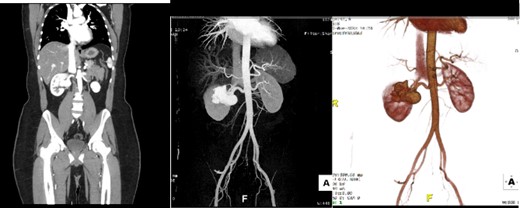

A 32-year-old male with no known chronic illnesses had a history of a motor vehicle accident five years ago, resulting in multiple bilateral rib fractures. An abdominal and pelvic CT scan conducted at the time did not reveal any other findings. The patient was admitted under the care of thoracic surgery for observation and pain management. After four years from the accident, the patient experienced intermittent right flank pain and made multiple visits to the emergency room. A CT scan of the kidneys, ureters, and bladder (CT KUB) was performed to rule out urolithiasis. The CT KUB showed multiple prominent structures with communication between the arterial and venous systems at the right renal hilum, suggestive of an intrarenal AVM with no apparent complications (Fig. 1). A CT run-off study confirmed the presence of an intrarenal AVM in the upper pole, measuring 2.9 cm (Fig. 2). The patient underwent angioembolization; however, multiple attempts at coil embolization failed due to the high risk of distal embolization. Subsequently, the patient underwent exploratory laparotomy for right AVF ligation. During the procedure, three AVF tracts were identified and ligated using clips. Prior to ligation, a thrill was palpable, but it was absent after the ligation. On the second postoperative day, a Doppler renal US was performed, which revealed patent right intrarenal arteries with normal resistive indices and normal peak systolic velocity in the right main renal arteries.

CT KUB showed multiple prominent structures with communication between the arterial and venous systems at the right renal hilum, suggestive of an intrarenal arteriovenous malformation (AVM).